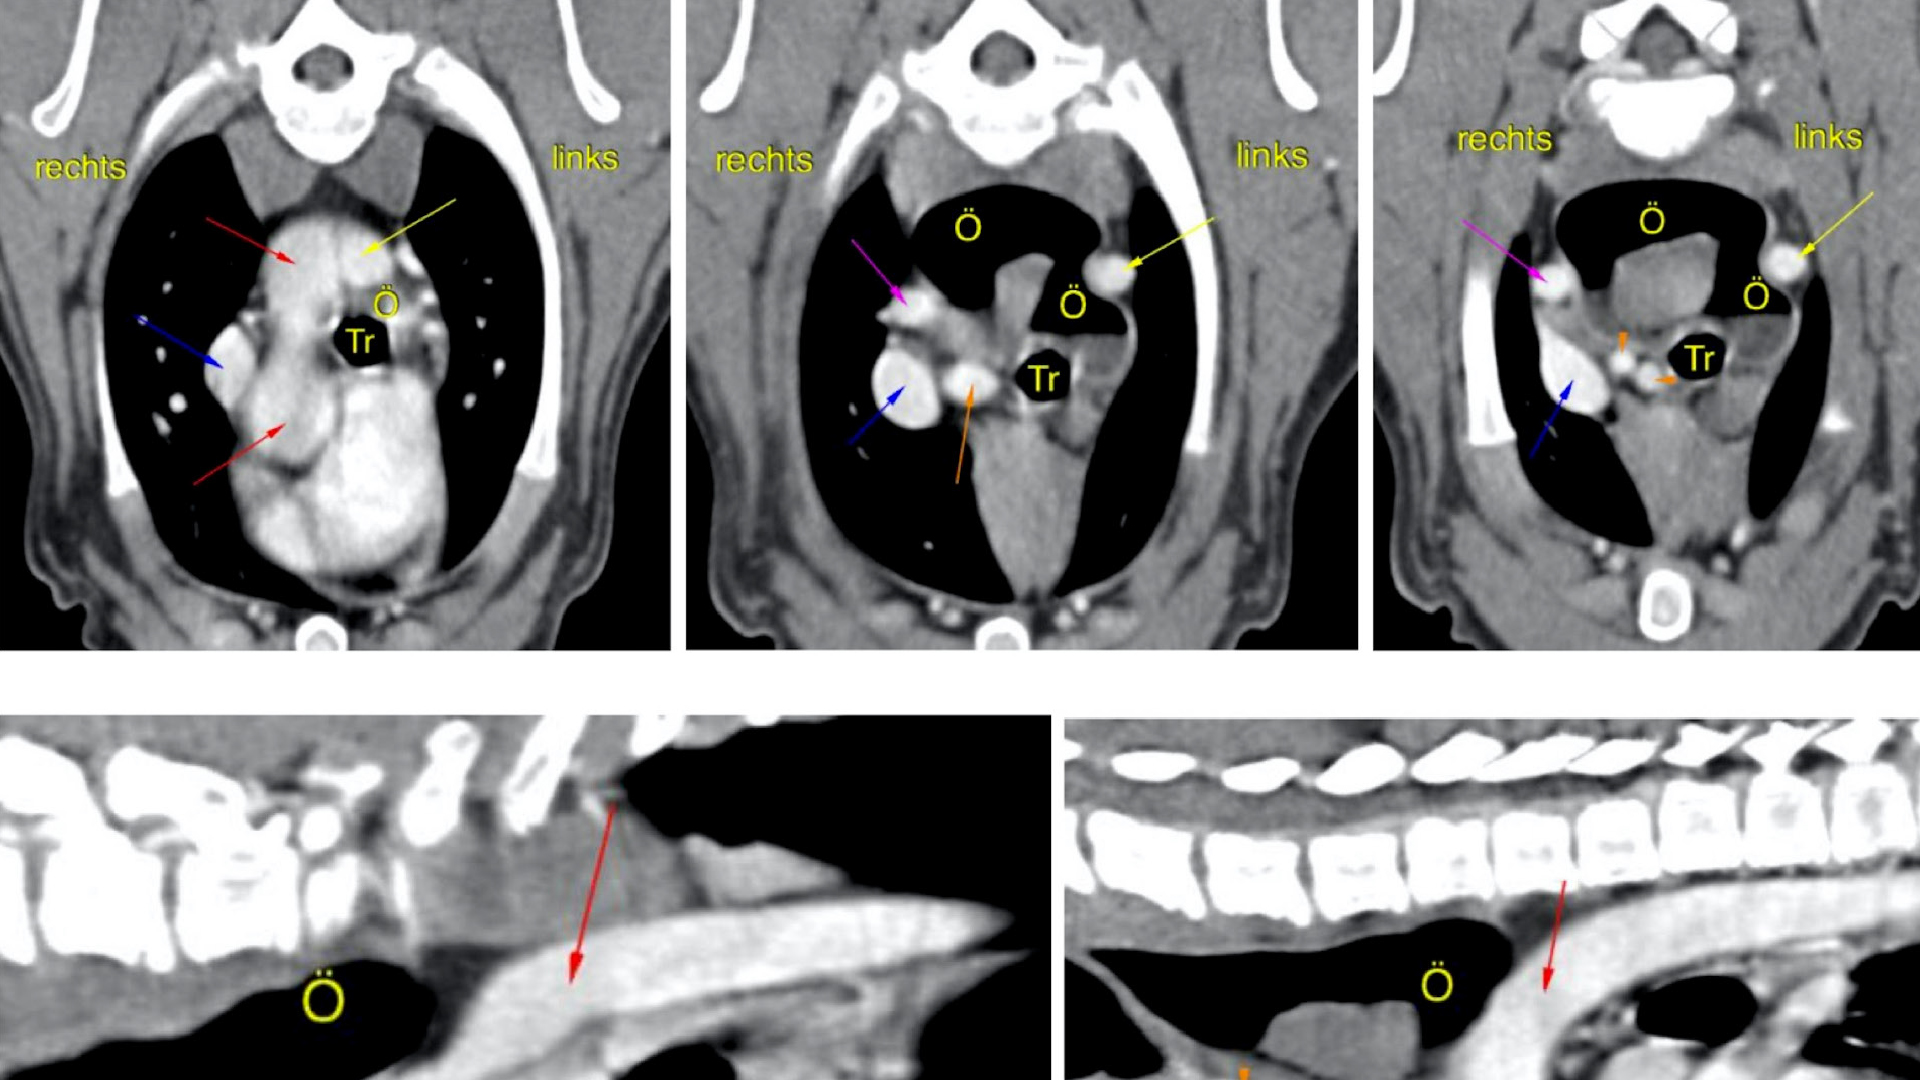

Um den Verdacht des PRAA zu bestätigen bzw. um andere vaskuläre Ringanomalien zu detektieren, wurde weiterführend eine computertomografische Untersuchung des Thorax durchgeführt. Es wurden eine frühe arterielle (nach zehn bis 20 Sekunden) und jeweils zwei venöse Kontrastmittelserien (nach 60 und 120 Sekunden) angefertigt. Das CT des Thorax zeigte (Abb. 3) einen persistierenden rechten Aortenbogen mit aberranter A. subclavia sinistra (vaskuläre Ringanomalie Typ 2) sowie eine sekundäre fokale Ösophagusdilatation cranial der Kompressionsstelle. Weitere – klinisch wahrscheinlich nicht relevante – Gefäßanomalien waren ein fehlender Truncus brachiocephalicus, ein existierender Truncus bicaroticus sowie eine A. carotis communis sinistra et dextra direkt aus dem Aortenbogen und eine aberrante rechte A. subclavia dextra. Ein persistierendes Lig. arteriosum konnte nicht eindeutig dargestellt werden, aufgrund der Studienlage wurde trotzdem eine vaskuläre Ringanomalie Typ 3 nicht ausgeschlossen.